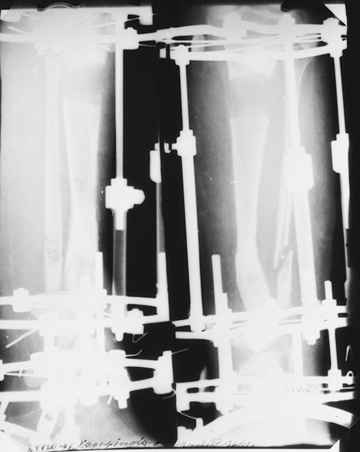

На втором этапе произведёно освежение краёв костных фрагментов б/б и м/б костей с приданием проксимальному фрагменту б/б кости впалой, а дистальному выпуклой формы, открытие канала проксимального фрагмента и погружной остеосинтез, а также остеотомия б/б кости в в/3 и м/б кости на границе с/3 и н/3 голени. Больной проводился одновременный бифокальный компрессионно-дистракционный остеосинтез. Достигнуто 11 см. удлинение и сращение ВПГ.

Срок лечения 11 месяцев. Наблюдение 2 года.

100% сращение. У 2 –х была повторная операция из-за рецидива, причиной которого было сращение с деформацией.